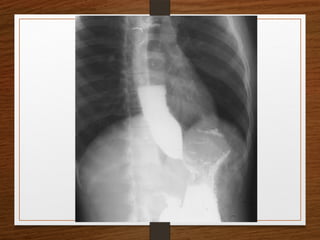

• Barium Swallow

• Achalasia

• Ca Esophagus

Contrast Films

• Barium Meal

• Barium Enema

• IVP

Barium Studies

Barium studies can demonstrate GI abnormalities in three ways

1. Mucosal relief views of the collapsed or partially collapsed

lumen obtained with a small volume of barium.

• particularly useful for showing abnormalities involving the

submucosa, such as esophageal varices.

2. Single-contrast views of the filled lumen obtained with a

large volume of low-density barium

• These views enable visualization of contour abnormalities,

strictures, and large polypoid defects.

3. Double-contrast views obtained after the mucosal surface

has been coated with a thin layer of high-density barium

and the lumen has been distended with gas

• These views enable visualization of subtle mucosal lesions, such as

the early changes of inflammatory bowel disease and early

neoplastic lesions

• Barium suspensions for single-contrast studies

should be of moderate density (50%-100% w/v)

when not diluted.

• For the double-contrast examination, we use high-

density 250% w/v barium